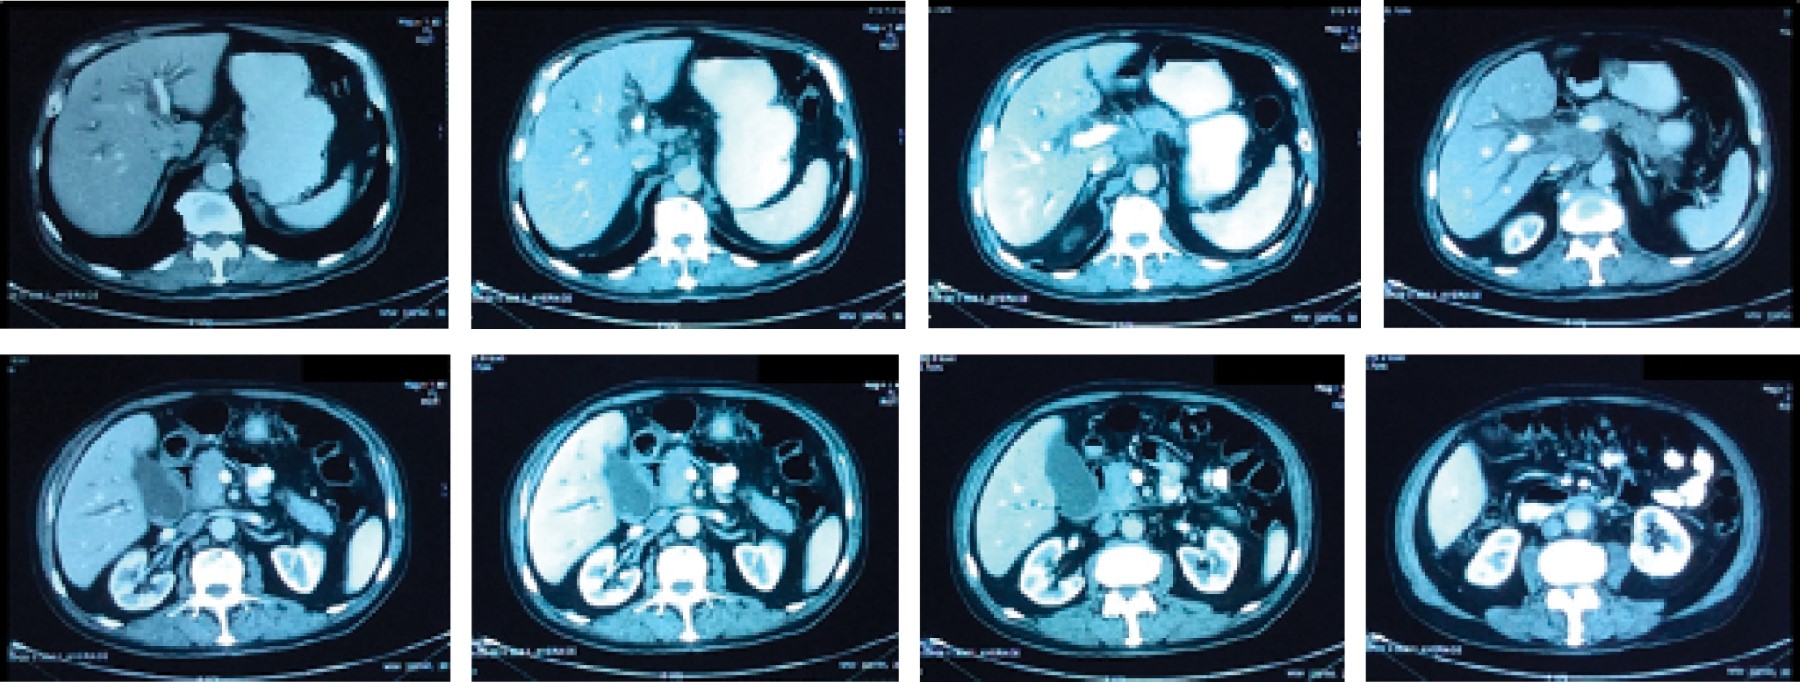

A CT scan was performed and reported (Figure 2): "...marked dilatation of the intrahepatic biliary tract, left hepatic of 13 mm, right hepatic of 14 mm, common hepatic duct of 16 mm and cystic duct of 9 mm. There is apparent stenosis of the common hepatic and cystic ducts. No common bile duct is observed; in topography, there is an irregular image of solid appearance, with partially defined contours, with heterogeneous intensification after the administration of contrast medium, which measures 61 × 30 mm and is accompanied by lymphadenopathy at the level of the hepatic hilum. Diagnostic impression: tomographic data suggestive of neoplastic process at the level of the hepatic hilum, which conditions intrahepatic cholestasis, and may correspond to Klatskin's tumor without being able to rule out an inflammatory process".

Figure 2